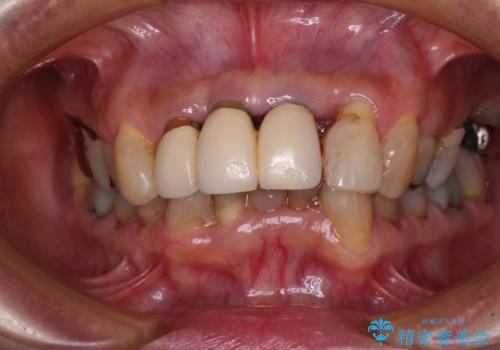

- 上顎前歯の違和感や不快感を気にして来院された患者様です。

現在のクラウンは金属の縁が見えており、歯と歯と歯肉の間に大きなスペースができていて、見た目も悪く、物が挟まったり話しにくかったりしていました。

また、前歯に抜歯が必要な歯があったため、抜歯をし、傷の治りを待ってオールセラミックブリッジにて補綴治療を行うこととしました。